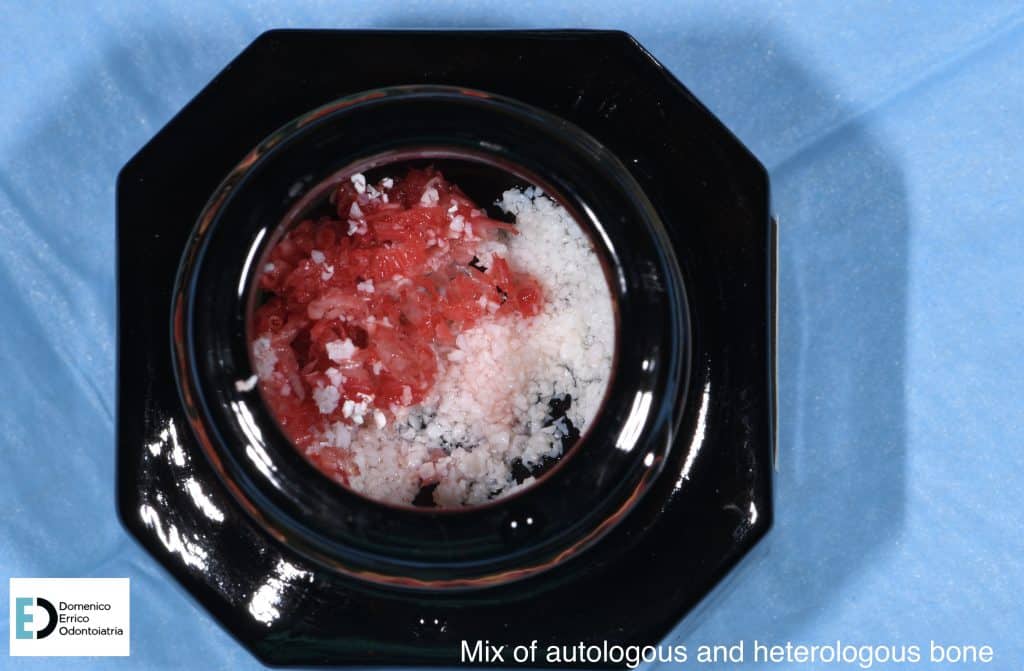

The treatment objectives are primarily functional: the restoration of volumes, necessary for implant rehabilitation due to insufficient bone height for fixture placement applying a mesh with a filler, consisting of 50% autologous bone and 50% heterologous bone; the reinstatement of chewing function by a second intervention to remove the mesh and simultaneously place two implant fixtures, concurrent with an increase of adherent gingival tissue level; and finally, the goal is to achieve the correct vertical relationship between the upper and lower arches through prosthetic rehabilitation of the upper arch with the replacement of the old prosthetic device.